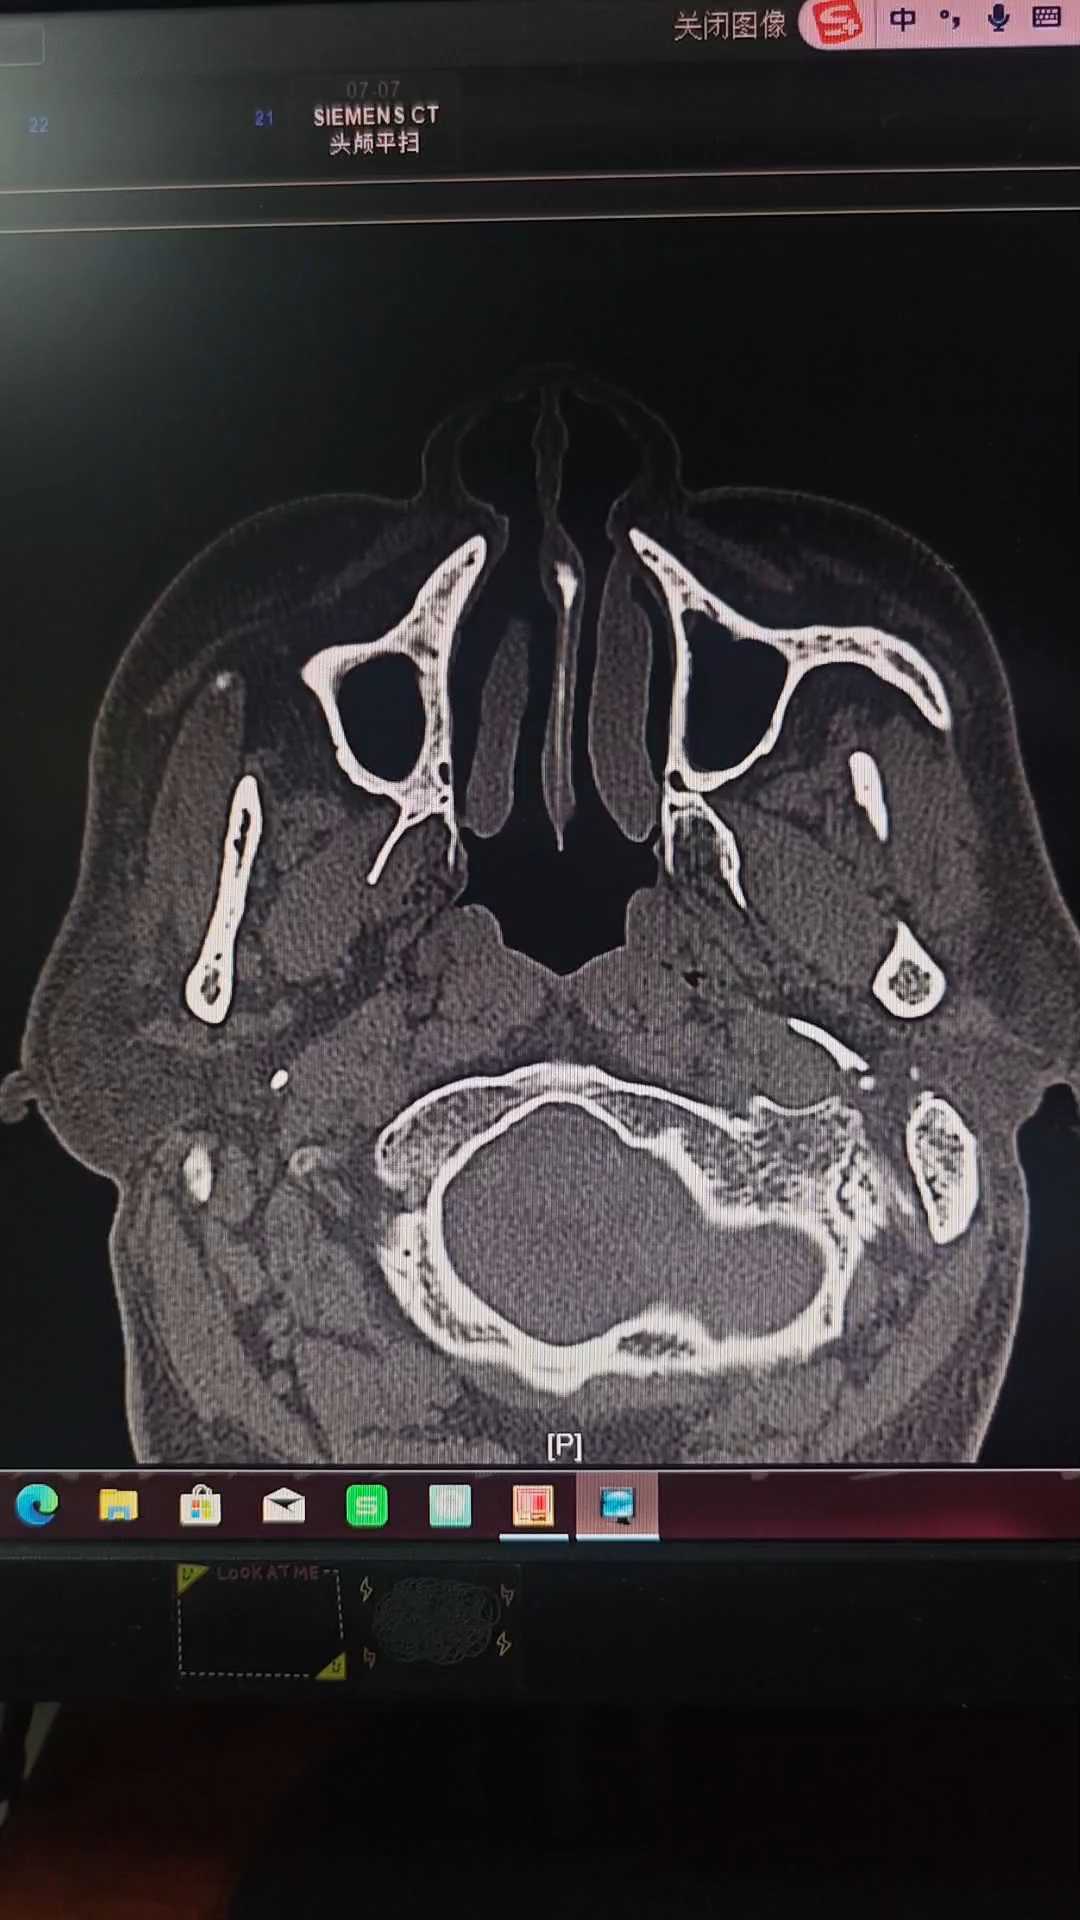

患者男性,60岁,一月前无诱因出现右耳内异常响声,进食咀嚼时出现,无耳痛、耳流脓、流血、听力下降症状。

外耳道前壁局部随咀嚼或讲话膨出活动